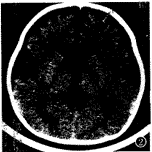

图2 外部性脑积水:额顶区蛛网膜下 腔对称性增宽,宽度达10mm,额顶区大脑沟增宽加深,大脑半球间裂前部增宽,侧脑室扩大 。

3个月内复查CT 30例,CT表现异常19例,其中2个月内复查CT时,12例侧脑室后角或前、后 角周围白质内仍可见斑片状低密度灶。外部性脑积水(EH)1例,CT表现为:额顶区蛛网膜下 腔对称性增宽,宽度≥5mm,大脑半球间裂前部增宽,额顶区大脑沟增宽加深,脑基底池主 要是鞍上池增大,脑室不大或轻度扩大[5,6](图2)。脑室周围白质软化症(PVL)3 例,其中脑软化和脑萎缩1例,结合文献[7],PVL可分为轻、中、重3度,CT诊断 标准为:侧脑室周围白质明显对称性减少或消失,外侧裂池部位脑沟加深,脑灰质逼近侧脑 室缘,与侧脑室缘的距离甚小或消失,侧脑室不同程度扩大,以后角、三角区明显,侧脑 室缘不规整(图3),侧脑室后角或前、后角周围白质内可见斑片状低密度灶。脑积水2例,脑 软化1例。